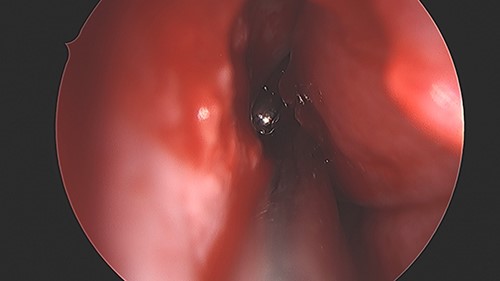

An 11 year-old male was transferred to the emergency room after being shot with a BB gun while playing. The patient’s custodian reports that he returned home with severe bleeding from bilateral nostrils which spontaneously resolved. The patient denies postnasal drip or salty taste. His medical history includes bipolar disorder and attention-deficit disorder managed with medications. On physical examination, an entry point wound is noticed in the skin of the left nasal sidewall (Figs 1 and 2). No active bleeding is noticed from anterior nasoscopy or in the posterior oropharynx exam. The rest of the head and neck examination is unremarkable. Plain X-rays performed in the emergency room confirm the presence of a metallic object in the right nasal cavity/paranasal sinuses (Figs 3 and 4). After consent is obtained, the patient is taken to the operating room and nasal endoscopy is performed. The left nasal cavity appears unremarkable. In the posterior nasal cavity, minimal bleeding and avulsed tissue is noticed after medialization of the middle turbinate. After minimal removal of tissue with pediatric Blakesley forceps, the BB bullet is visualized as lodged in the right posterior nasal cavity adjacent to the posterior attachment of the middle turbinate (Fig. 5). The bullet was then grasped with Takahashi forceps and removed after minimal endoscopic dissection (Fig. 6). Following extubation, the patient was observed for 8 h prior to discharge. During this period, no signs of recurrent epistaxis or cerebrospinal fluid rhinorrea were noticed.

Finally, the trajectory of a projectile can be extremely unpredictable. In our case, the bullet passed from the skin of the left nasal sidewall in a posterior and inferior direction ending in the posterior ethmoids, just adjacent to the posterior attachment of the right middle turbinate in the territory of the sphenopalatine vessels. Surprisingly, no bleeding was noticed in the left nasal cavity during the nasal endoscopy. Penetration of the posterior septum in a full thickness manner was then identified, which was considered of no clinical significance and no specific action was taken.